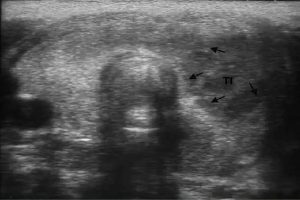

El programa fue diseñado para llevar de la mano al participante y ofrecerle herramientas que le permitan hacer una evaluación radiológica atinada, lo cual lo llevará a un diagnóstico que por ende arrojará el tratamiento idóneo. El énfasis se ha dado en la metodología diagnóstica, que es por inducción, así como el manejo del paciente, para crear una conciencia responsable y humana entre los que se dedican o quieren iniciarse en la práctica de la ultrasonografía. Dado a que existe una aplastante demanda de estudios de ultrasonido ante el insuficiente número de médicos radiólogos certificados, además de que el servicio de rayos x en México ha sufrido de ineficiencia en la aplicación del estudio y elaboración diagnóstica de la patología, la labor de este curso es formar de manera profesional a los médicos para que cubran y aminore en gran medida este problema que habita en el sector de salud.